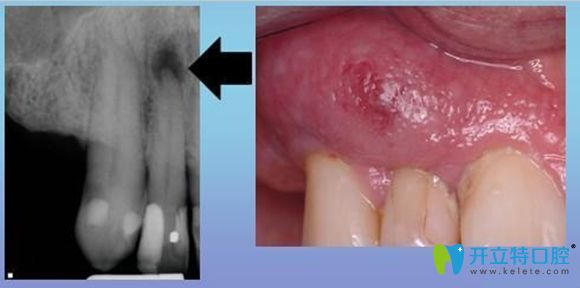

牙齦瘺管它是一種常見的口腔疾病,其形成的原因很多,但是主要原因多是根尖周炎引起的。

它的臨床癥狀多表現(xiàn)為,患牙根部位置會(huì)先出現(xiàn)一個(gè)腫包,然后這個(gè)包會(huì)逐漸變大,并伴隨著分泌物溢出。

是因?yàn)榧毙愿庵苎装Y形成膿腫,膿液引流不暢,往外排出導(dǎo)致的,也可以說是根尖周炎癥常見的一種排膿途徑。

牙齦瘺管癥狀示意圖